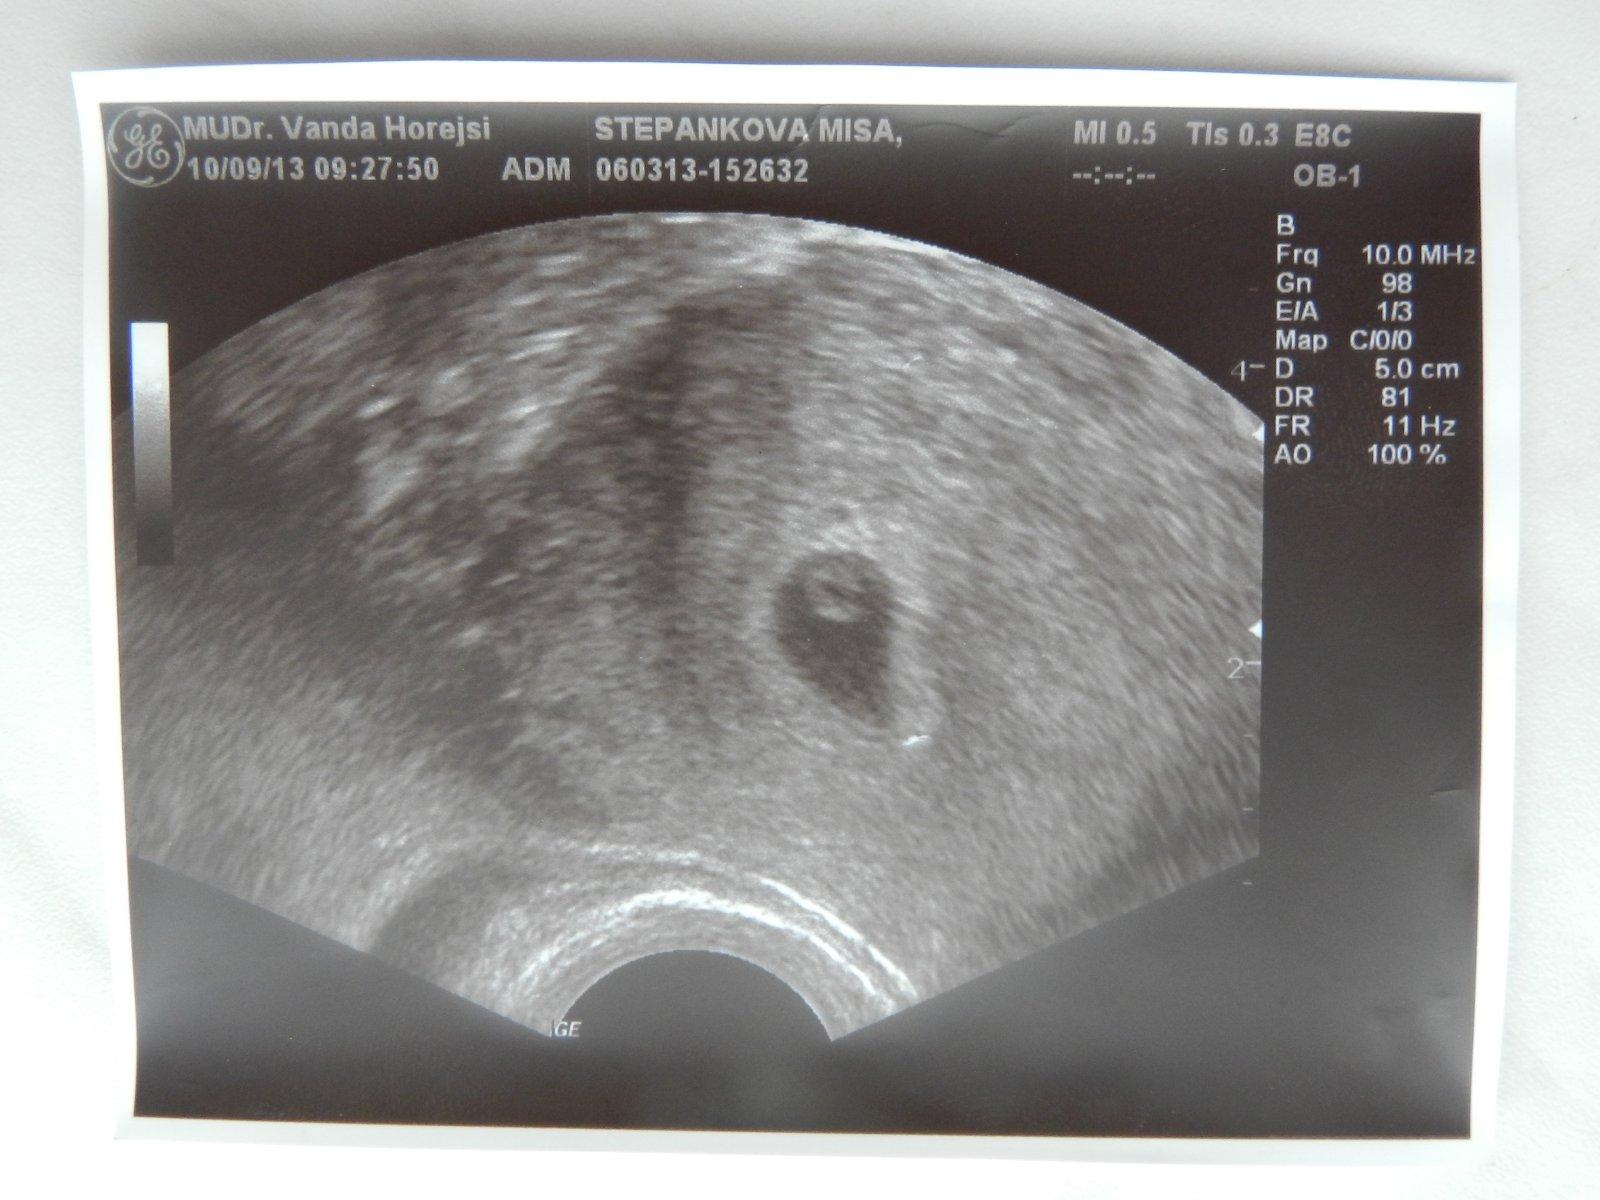

ahojky holky, nevím do jaké diskuze se s mým problémem vrtnou a ani nevím, jak se zakládá další, tak prosím o radu tady 🙂 Přidávám foto našich údajně dvojčat. foto bylo focena 6+3, ale dr mi řekl, že to odpovídá na 5týden. Jaký máte názor na ten plod? Myslím si, že kdyby měl lepší přístroj a mohl to víc přiblížit, že by stáří odpovídalo podle MS. a druhý váček se tam udělal během týdne a to se neví, jestli je to vytrácející se dvojče, nebo jestli se jen oplodnilo dýl. Jaký máte na fotku názory? Mohlo by být mimi starší, než tvrdí doktor? (mě přijde, že v tom jednom váčku už je docela větší kus bílý, tak že by to mohlo být už embrio) díky všem a pokud někdo dodá odkaz na lepší diskuzi, budu ráda 🙂

@miky00 ahojky mě se zdá,že to dvojče mizí bohužel ☹ a vůbec nevadí,že jsi o týden méně 🙂 a taky v tom druhém vidím asi plůdek 🙂 🙂 já taky toto těhu čekala dvojčátka,první týden na potvrzení těhu tam byl jen jeden váček,týden na to už 2 a další týden na to zase jeden a bylo už i srdíčko ♥ moc držím palečky aby ten jeden bojovníček byl tak jako náš Maty a bylo vše v naprostém pořádku... tato fotka je myslím s 4+6tt 😀